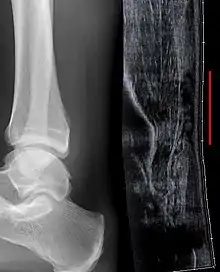

Although a tear may be diagnosed by history and physical exam alone, an ultrasound scan is sometimes required to clarify or confirm the diagnosis. Once diagnosis is made, ultrasound imaging is an effective way to monitor the healing progress of the tendon over time. An ultrasound is recommended over MRI and MRI is generally not needed.[11][14] Both MRI and ultrasound are effective tools and have their strengths and limitations. However, when it comes to an Achilles tendon tear, an ultrasound is usually recommended first because of convenience, quick availability, and cost.[15]

Ultrasonography can be used to determine the tendon thickness, character, and presence of a tear. It works by sending harmless high frequencies of sound waves through the body. Some of these sound waves reflect back off the spaces between fluid and soft tissue or bone. These reflected images are analyzed and created into an image. These images capture in real time and are helpful in detecting movement of the tendon and visualizing injuries or tears. This device makes it possible to identify injuries and observe healing over time. Ultrasound is inexpensive and involves no harmful radiation. It is operator-dependent and so requires a level of skill and practice for it to be used effectively.[15]

MRI can be used to distinguish incomplete ruptures from degeneration of the Achilles tendon. MRI can also distinguish between paratenonitis, tendinosis, and bursitis. This technique uses a strong uniform magnetic field to align millions of protons running through the body. These protons are then bombarded with radio waves that knock some of them out of alignment. When these protons return they emit their own unique radio waves that is analyzed by a computer in 3D to create a sharp cross sectional image of the area. MRI provides excellent soft tissue imaging making it easier for technicians to spot tears or other injuries.[16]

Radiography can also be used to indirectly identify Achilles tendon tears. Radiography uses X-rays to analyze the point of injury. This is not very effective at identifying soft tissue injuries. X-rays are created when high energy electrons hit a metal source. X-ray images are acquired by utilizing the different densities of the bone or tissue. When these rays pass through tissue they are captured on film. X-rays are generally best for dense objects such as bone while soft tissue is shown poorly. Radiography is not the best for assessing an Achilles tendon injury. It is more useful for ruling out other injuries such as heal bone fractures.[14]